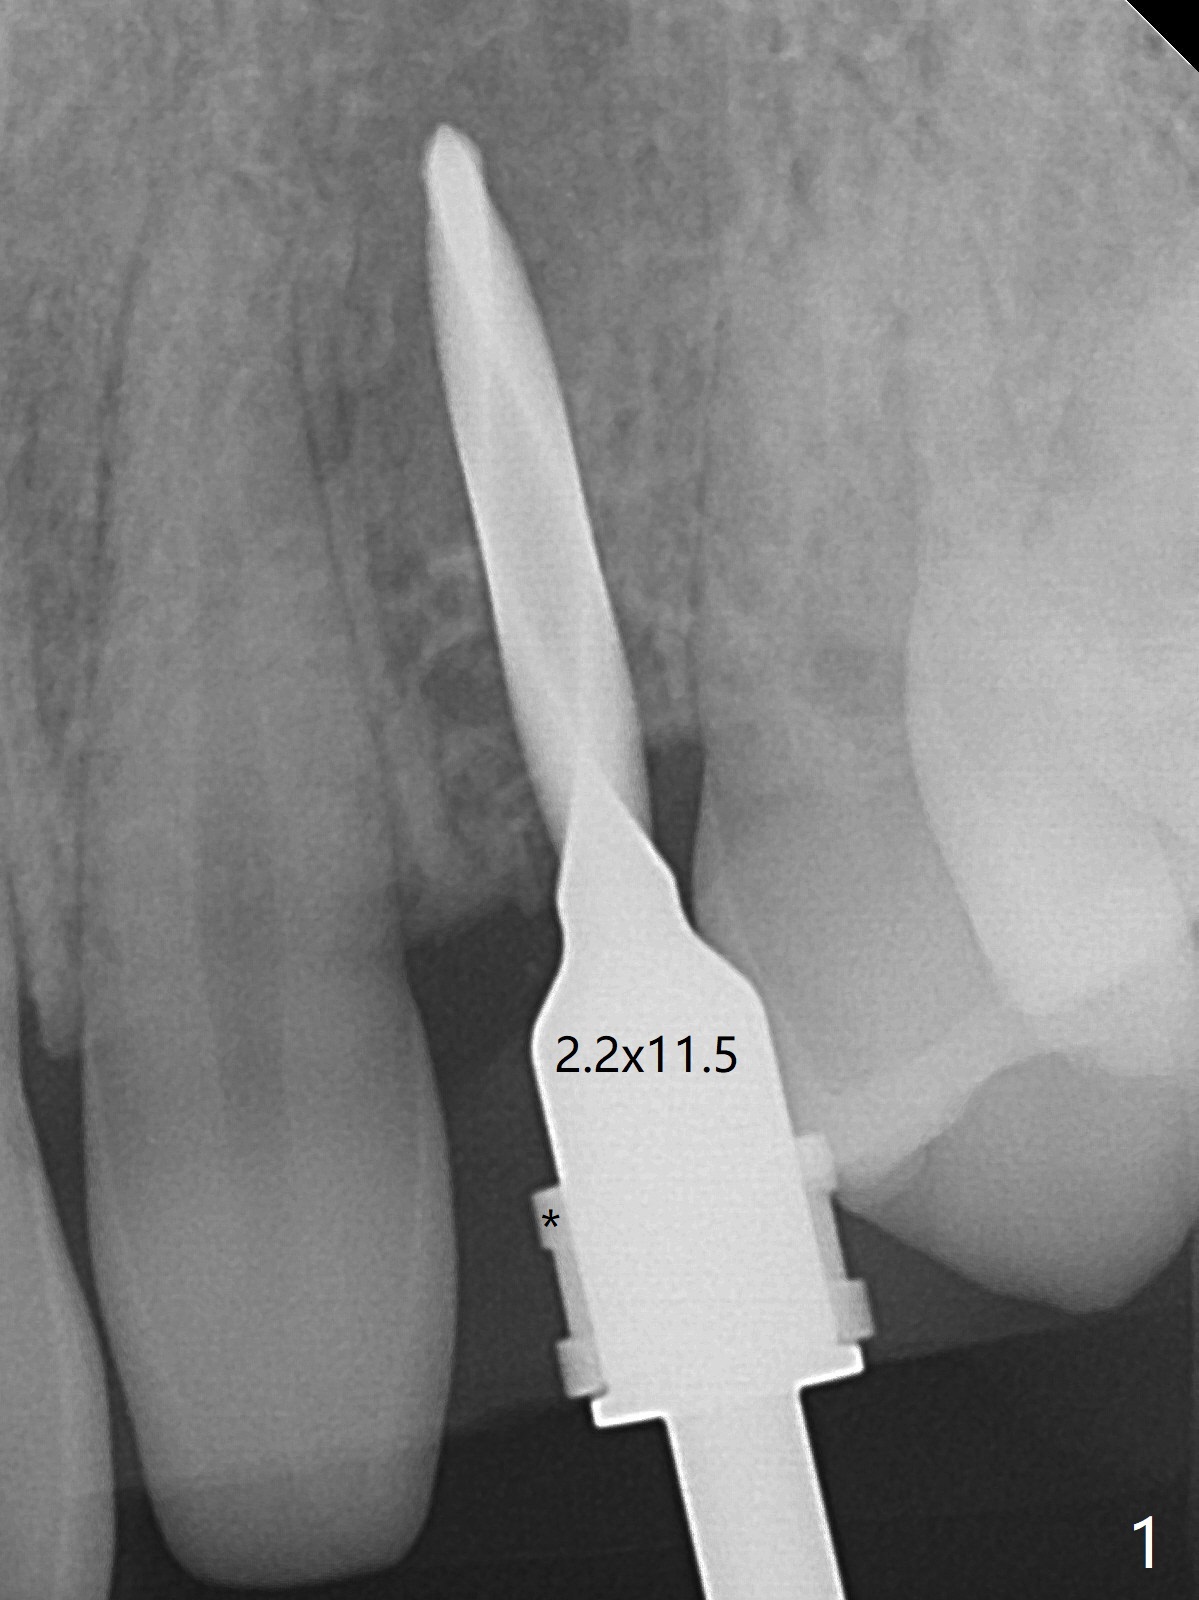

When the guide with 10.5 mm offset is seated at #11 after extraction, it looks buccal. Pointed drill creates an entry point in the mesial portion of the socket. PA, taken following 2.2x11.5 mm drill, shows acceptable mesiodistal trajectory (Fig.1). When a 3.5x11.5 mm implant is placed, it is difficult to withdraw the driver from the metal tube (Fig.1 *). There is no buccal gap with plenty of the lingual gap. A 4x3 mm x15 degree A-type angled abutment is placed (Fig.2). It appears that the dense palatal plate deviates the osteotomy and implant placement (as compared to the design, Fig.3). In fact osteotomy should have been prepared until 4 mm in diameter before increase in depth with 2.2 and 3 mm drills to eliminate buccal deviation. The ideal drill sequence would be point drill, 2.2x8.5 mm drill, 3x8.5, 3.5x8.5, 2.2x10, 2.2x11.5, PA to confirm trajectory, 3x10, 3x11.5 and 3x13. Torque associated with implant placement is pure, not derived from friction between the driver and the metal tube. There is mesial crestal bone loss 4 months postop (Fig.4, as compared to immediate postop in Fig.2 (*)). Crestal bone loss does not get worse between 4 and 6.5 months postop (Fig.4,5). The bone density increases 8 months post cementation (Fig.6).